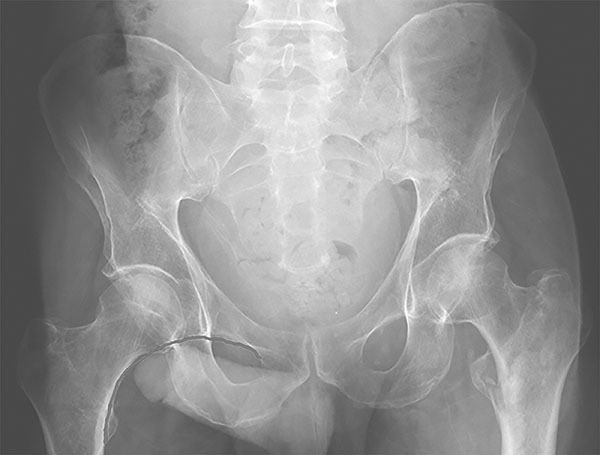

Falls are a significant mechanism for femur fractures in older adults, most commonly femoral neck and intertrochanteric fractures. Physical exam findings may include leg shortening, external rotation, severe pain to hip manipulation, and the inability to bear weight. Patients may complain of groin pain or knee pain, since these are common sites of referred pain.

Complete an evaluation of the femoral nerves with motor and sensory testing. X-rays are 90% to 98% sensitive for hip fractures, but occult fractures are best diagnosed by MRI if X-ray is nondiagnostic and pain continues. Evaluate pelvic X-rays for both Shenton line and neck-shaft angle within 120-130 degrees. (See Figure 1.)

Figure 1. Left Intertrochanteric Fracture with Shenton Line Demonstrated on the Right Side |

Image used with permission from Catherine Marco, MD, Wright State University Emergency Medicine |

Hemorrhage can be significant with intertrochanteric and subtrochanteric fractures; have a low threshold for blood product resuscitation. The most common complications during hospitalization after a hip fracture include venous thromboembolism and pulmonary infection, but femoral neck fractures can lead to avascular necrosis due to a risk for disruption of the medial and lateral femoral circumflex arteries.38 Consult anesthesia and orthopedic specialists because the best management is multidisciplinary with early surgical correction. Optimize the patient for surgery, including management of electrolyte imbalances and comorbid conditions.39 Fascia iliaca block has been shown to improve patient outcomes with fewer side effects than opiates.21